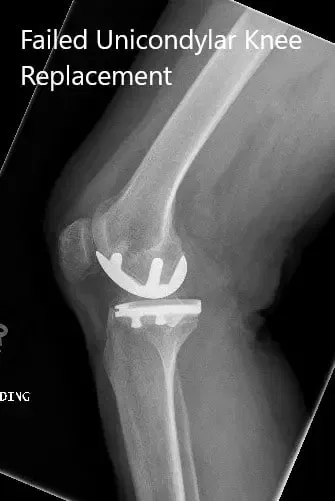

Radiografía preoperatoria de la rodilla derecha en vistas anteroposterior y lateral

DIAGNÓSTICO PREOPERATORIO: Reemplazo unilateral medial de rodilla fallido.